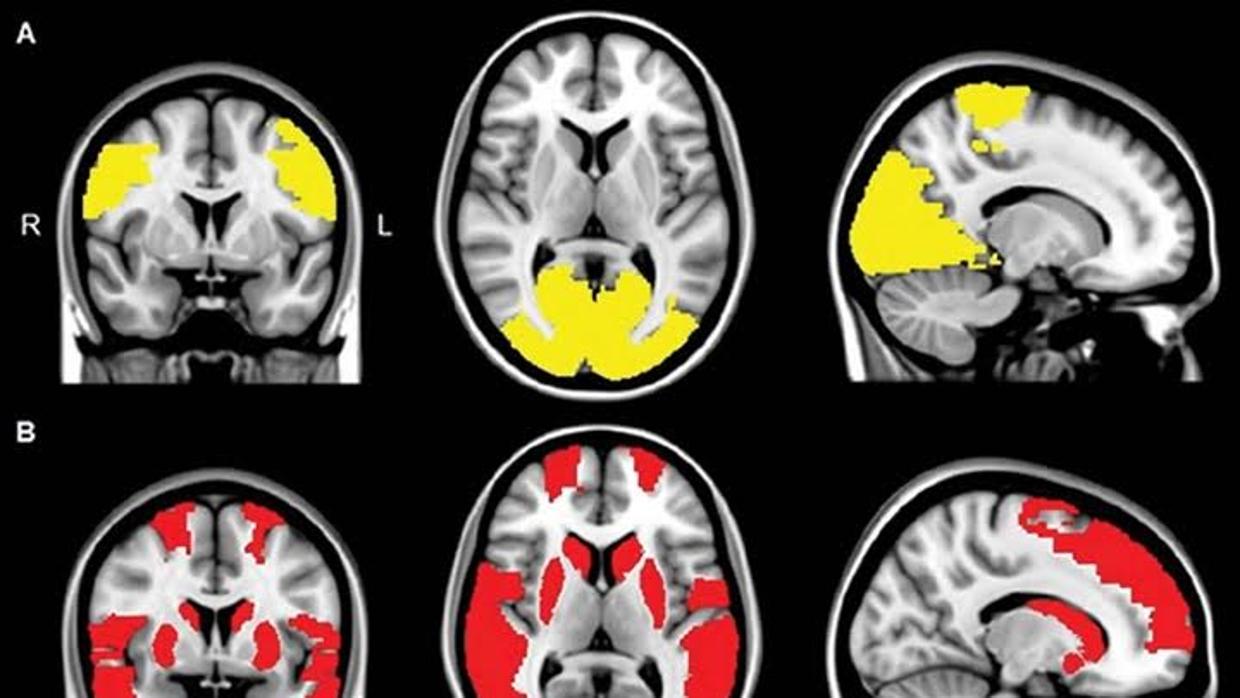

Disminución de la conectividad en los lóbulos paracentral y occipital en pacientes con alucinaciones visuales (abajo) VUMC

Los resultados mostraron que el grado de comunicación entre muchas de las áreas cerebrales era notablemente menor en los pacientes con párkinson que en los voluntarios sanos. Y asimismo, que comparados frente a los pacientes sin alteraciones perceptivas, la disminución en esta comunicación afectaba a algunas regiones cerebrales adicionales en aquellos que sufrían alucinaciones visuales, principalmente a las regiones implicadas en el mantenimiento de la atención y del procesamiento de la información visual .

En definitiva, parece que las alucinaciones visuales en la enfermedad de Parkinson son el resultado de una desconexión entre distintas regiones del cerebro. Como indica Menno M. Schoonheim, co-autor de la investigación, «hemos observado que las áreas cerebrales implicadas en la atención y en el procesamiento visual están menos conectadas con el resto del cerebro. Esto sugiere que la desconexión de estas áreas cerebrales puede contribuir al origen de este tipo de alteraciones perceptivas en los pacientes con párkinson».